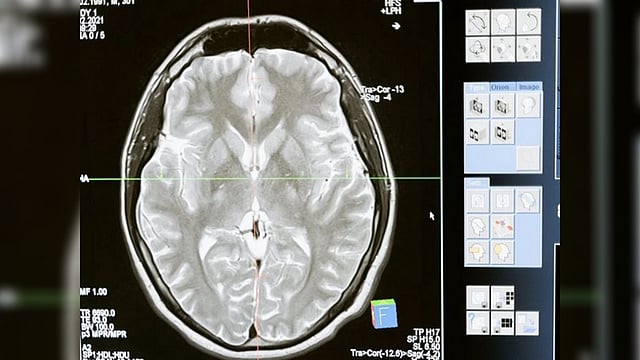

'New artificial model helps antibody-based treatments to reach brain'

UPPSALA [Sweden]: An artificial blood-brain barrier model that has been constructed by researchers at Uppsala University is quick and accurate, and it may be used to assess how well antibody-based treatments can reach the brain.

Protein-based biopharmaceuticals or biologics, such as antibodies, are promising therapeutic tools to specifically target clumps of protein found in neurodegenerative diseases such as Alzheimer's disease and Parkinson Disease.

However, the blood-brain barrier (BBB) provides a significant hurdle when trying to deliver biologics to areas of the brain to stop these large molecules causing disease.

Greta Hultqvist's research group at Uppsala University has recently published an article in Molecular Pharmaceutics highlighting the development of an artificial BBB model that can be used to determine how well antibody-based therapies can enter the brain.